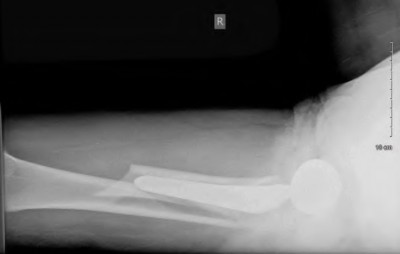

Question 94

During a total knee arthroplasty, which of the following surgical steps carries the highest risk of iatrogenic injury to the popliteal artery?

Explanation